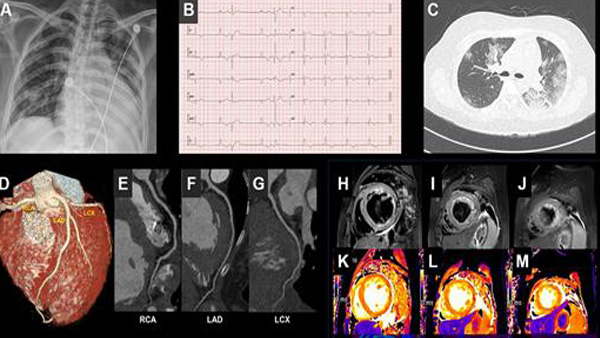

김인철 교수 등 계명대 동산병원 심장내과 연구팀은 확진 판정을 받은 뒤 급성 심근염 증상을 보인 21세 여성 사례를 국제학술지인 '유럽심장학회지' 최신호에서 공개했습니다.

이 환자는 확진 당시 기저질환이 없었으나 입원 후 심장이 비대해지고 심장 조직에 손상이 가는 증상 등으로 심근염 진단을 받았으며, 완치 판정을 받아 퇴원한 후에도 심장 기능이 완전히 회복되지 않았습니다.

연구팀은 심근염이 심해지면 흉통과 호흡 곤란이 발생하고, 계속 진행되면 만성 심부전으로 악화될 수 있다며, 코로나19 환자를 진료할 때 심근염 발생 여부를 주의 깊게 관찰해야 한다고 권고했습니다.